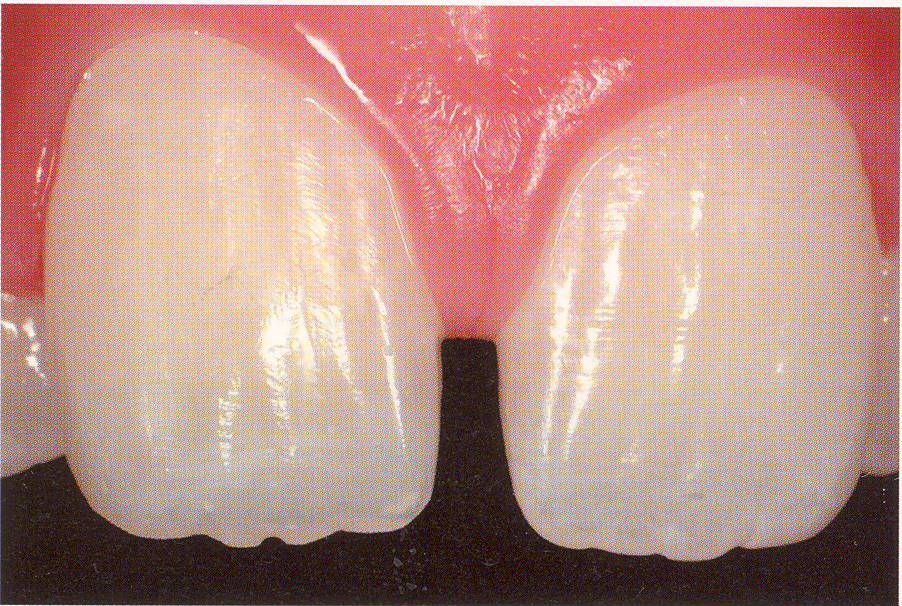

一応差し歯にしましたが、歯茎の状態はよくはありません。

とりあえず希望を入れて差し歯にしたような感じです。